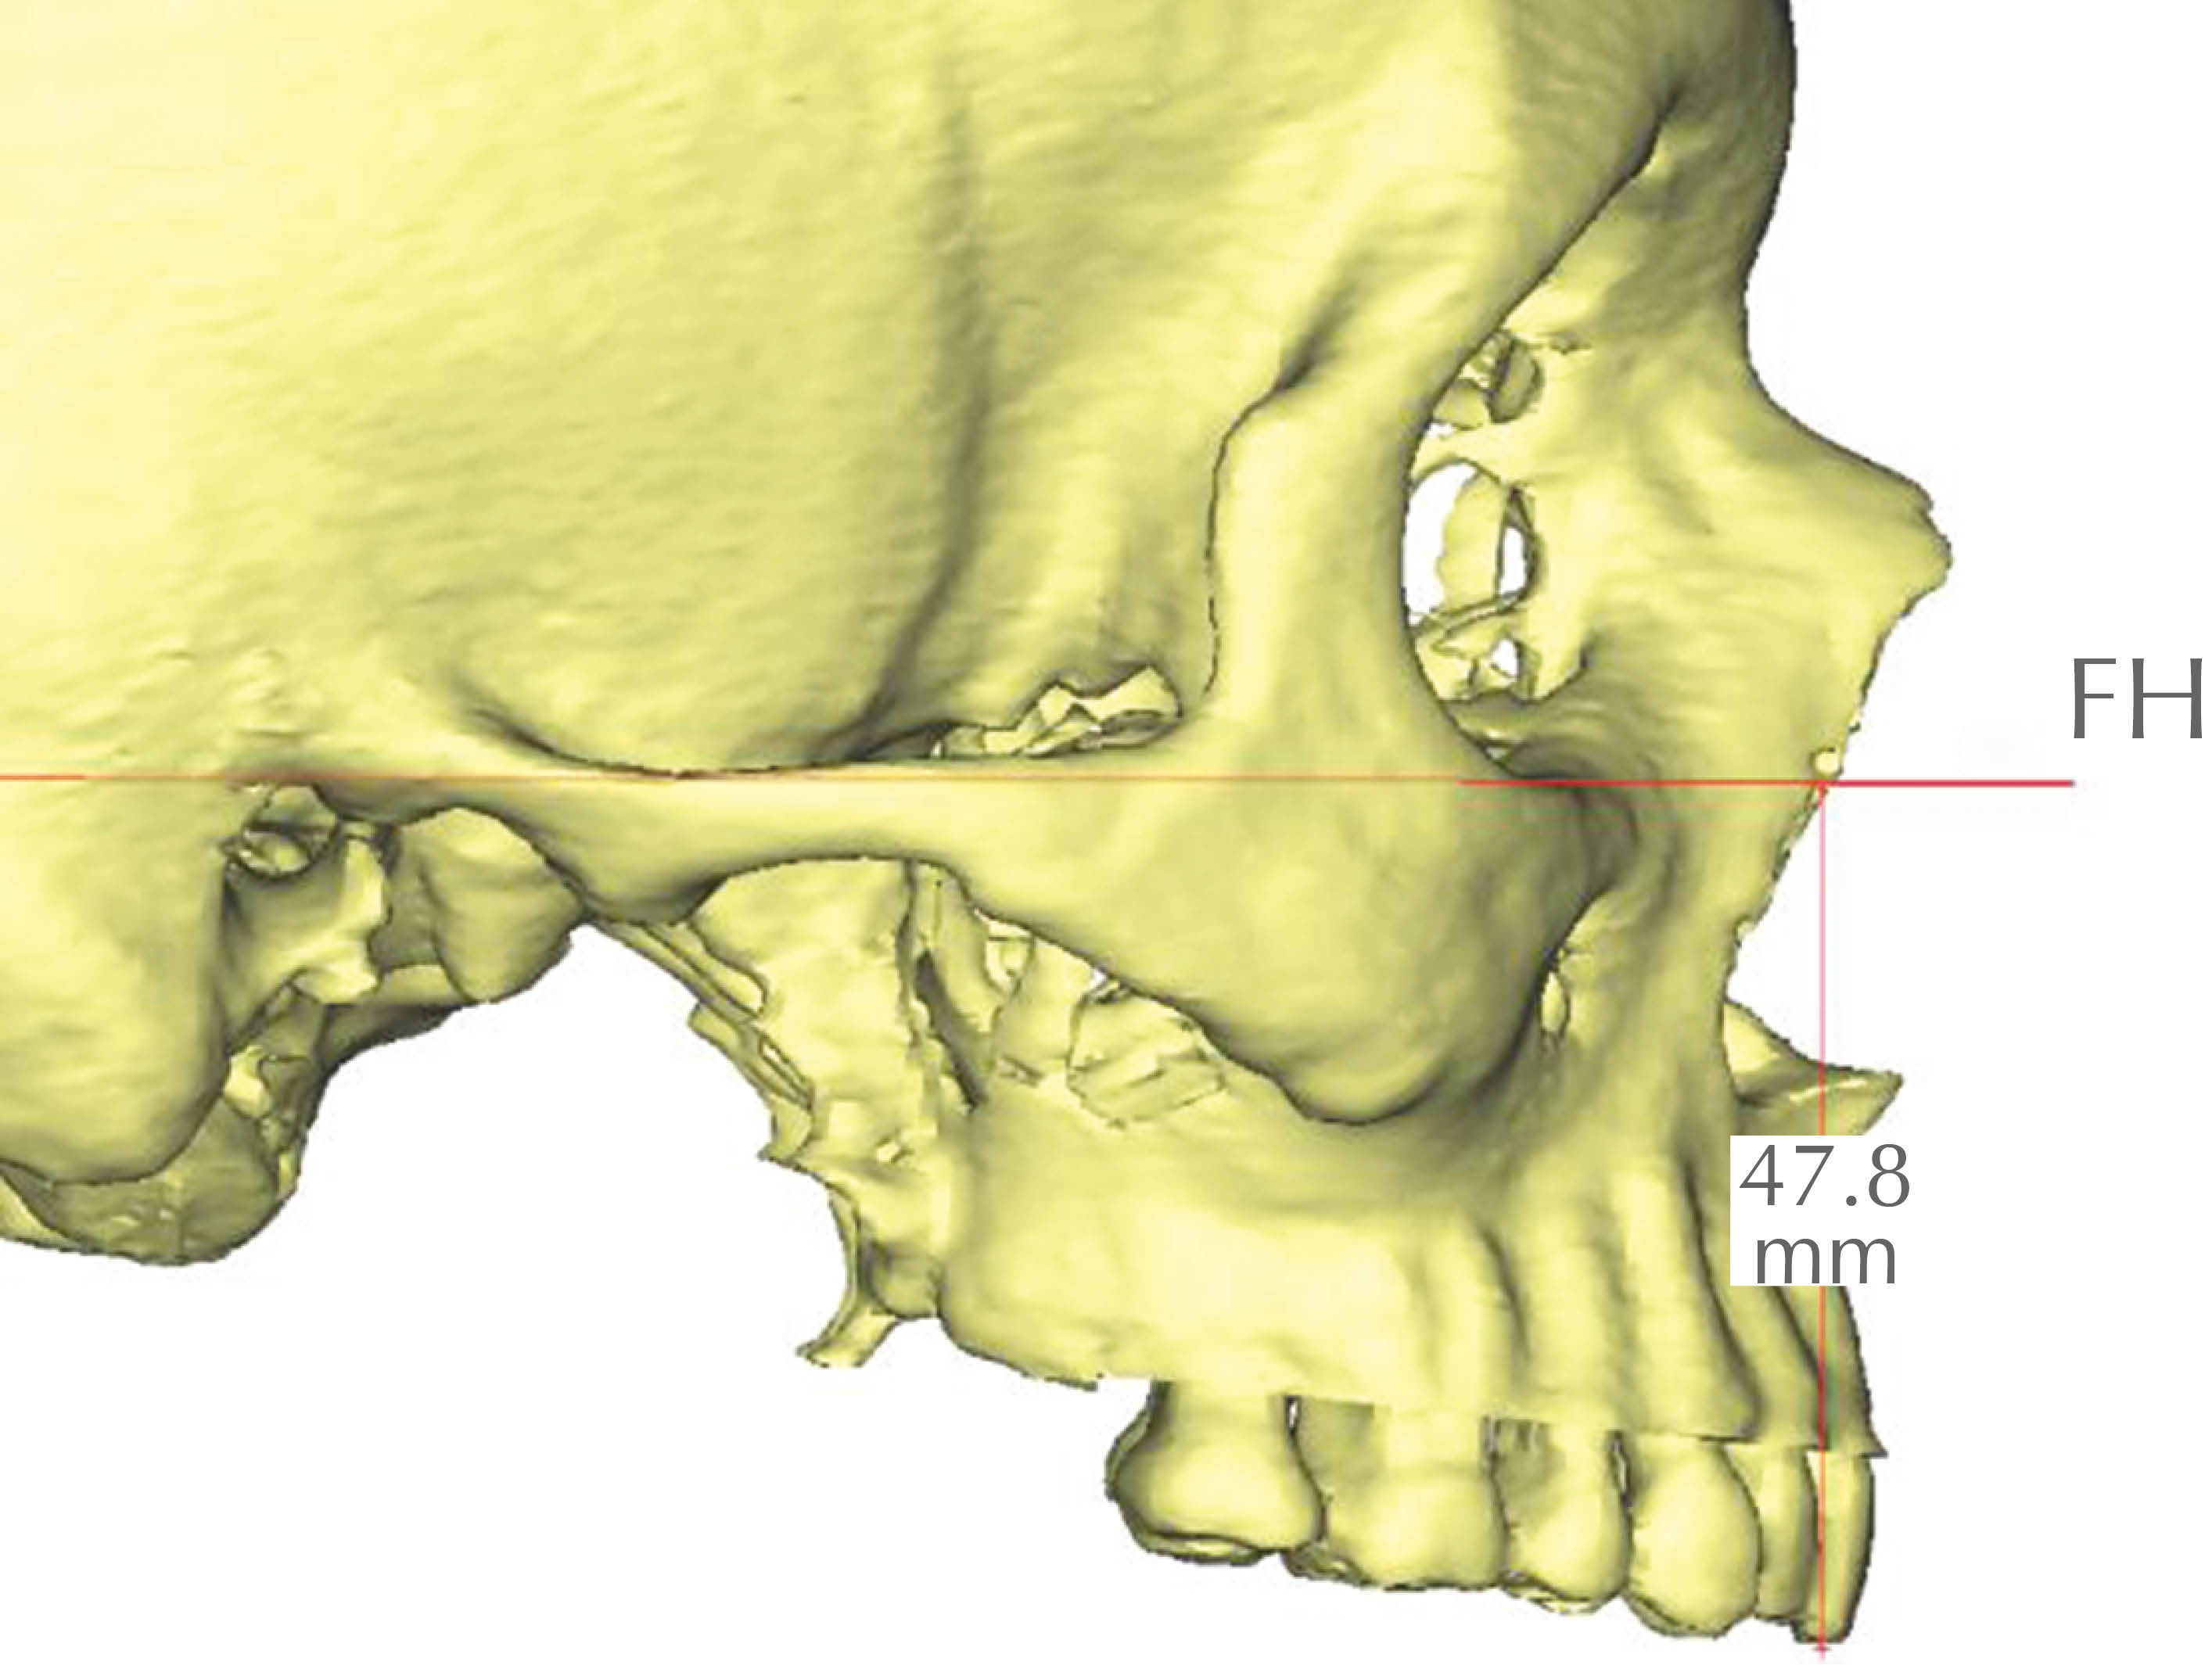

• 4. Mx-FH: posición media maxilar superoinferior; distancia entre el punto maxilar (Mx: punto equidistante entre la espina nasal anterior y la espina nasal posterior) y el plano horizontal de Frankfurt (Figura 11).

Figura 11